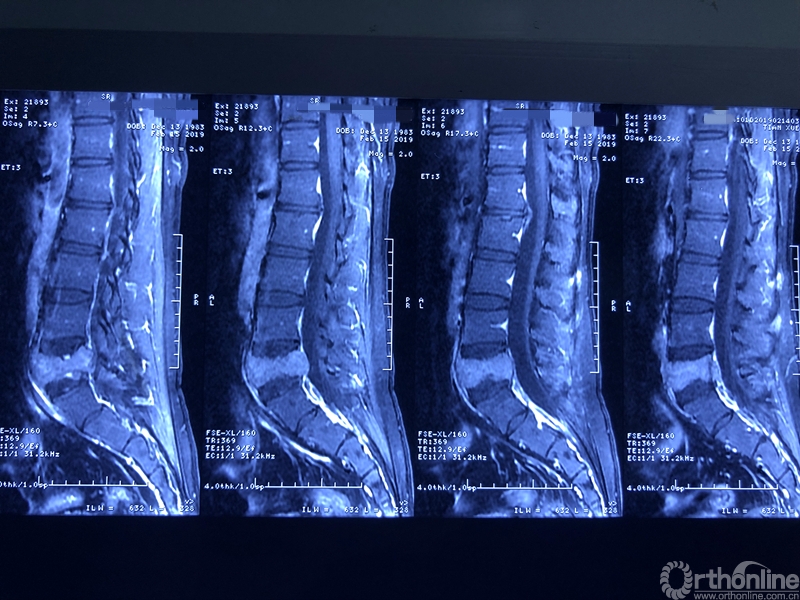

术前X线片

术前CT三维重建